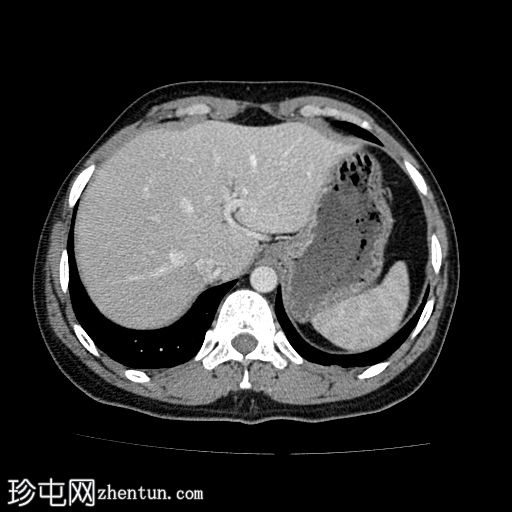

轴位增强扫描(门静脉期)

颈段和上胸段食管可见长段环周强化壁增厚,符合异物嵌顿引起的反应性水肿改变。

可见食管壁撕裂,可能与异物的方向有关。此外,可见多个食管周围气腔,提示可能存在食管穿孔。

未见纵隔积气、食管周围脓肿或明显穿孔的证据。